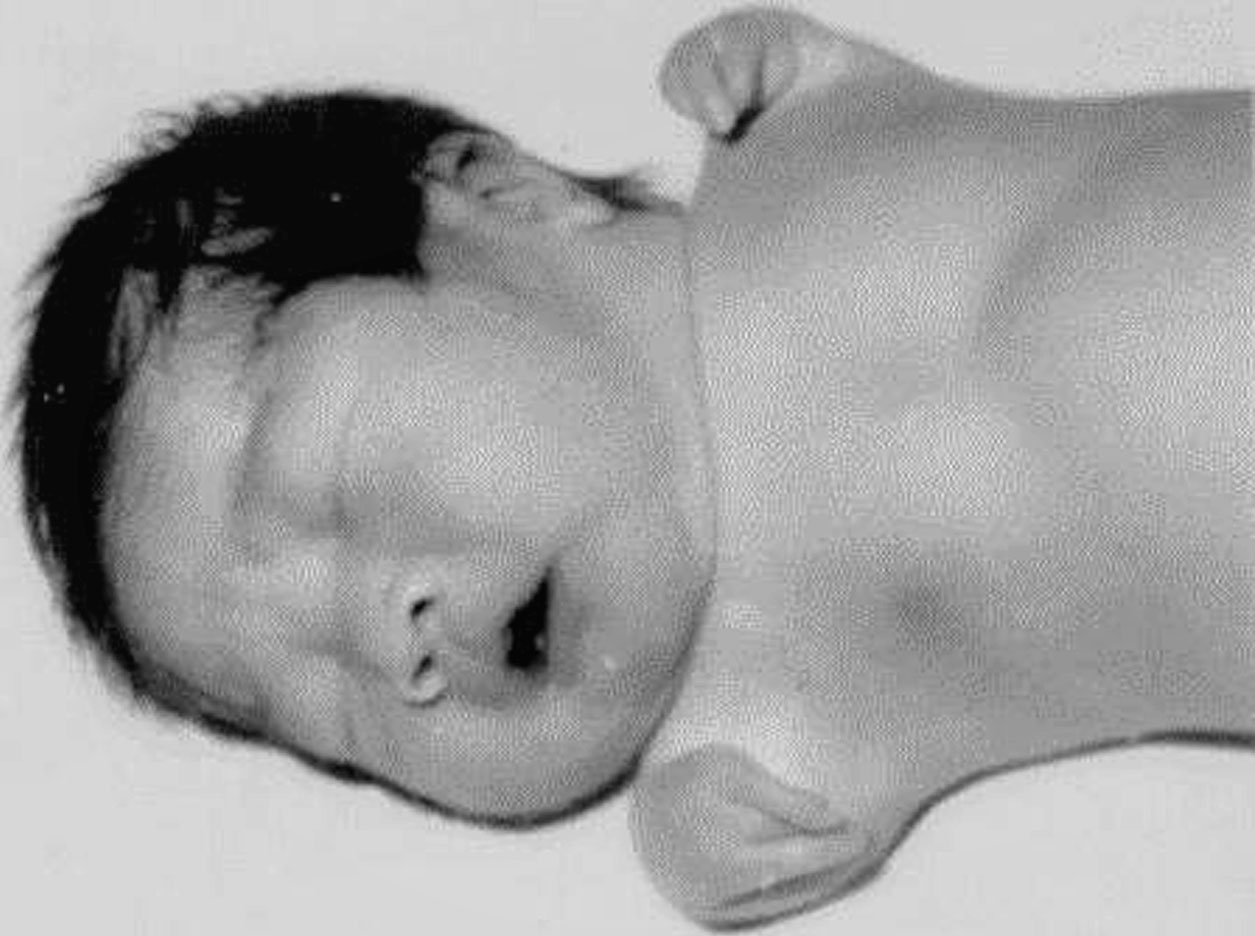

图1-2-12 完全性“海豹手”畸形